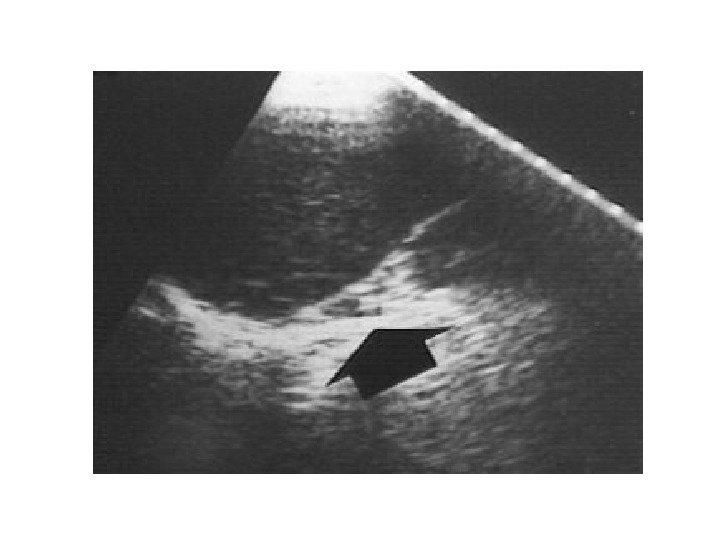

• В 10% случаев при феохромоцитоме компьютерная томография выявляет двустороннее поражение надпочечников. • Билатеральная феохромоцитома часто проявляется как незначительное увеличение надпочечников, с заметным повышением их васкуляризации. • Необходимо помнить, что феохромоцитома может иметь и вненадпочечниковую локализацию, располагаясь в паракавальных симпатических ганглиях, симпатических ганглиях средостения, ганглиях стенки мочевого пузыря.

• В 10% случаев при феохромоцитоме компьютерная томография выявляет двустороннее поражение надпочечников. • Билатеральная феохромоцитома часто проявляется как незначительное увеличение надпочечников, с заметным повышением их васкуляризации. • Необходимо помнить, что феохромоцитома может иметь и вненадпочечниковую локализацию, располагаясь в паракавальных симпатических ганглиях, симпатических ганглиях средостения, ганглиях стенки мочевого пузыря.

ФЕОХРОМОЦИТОМА

ФЕОХРОМОЦИТОМА